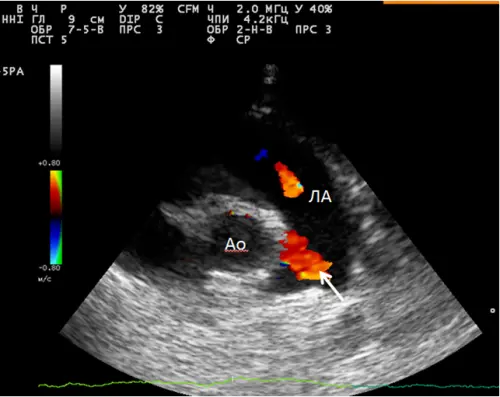

Вид дослідження визначає лікар — пацієнту обирати не потрібно. Але щоб розуміти, що відбувається на прийомі: стандартна ехокардіографія оцінює анатомію — розміри камер, будову клапанів, наявність дефектів перегородок. Це базовий протокол. Ехокардіографія з допплером додатково вимірює швидкість і характер кровотоку — незамінна при шумах і підозрі на клапанну патологію. ЕХО серця новонародженому — окремий протокол з урахуванням неонатальної фізіології: відкрита артеріальна протока, персистуюче овальне вікно, транзиторна легенева гіпертензія. Тривалість будь-якого з форматів — 20–35 хвилин.

Для дитячих досліджень використовується ультразвукова система [модель — уточнити у клініки] з високочастотним педіатричним датчиком. Режим кольорового допплерівського картування включений у стандартний протокол: саме він дозволяє виявити патологічний скид крові через дефекти перегородок, які у звичайному В-режимі можуть бути не видні.